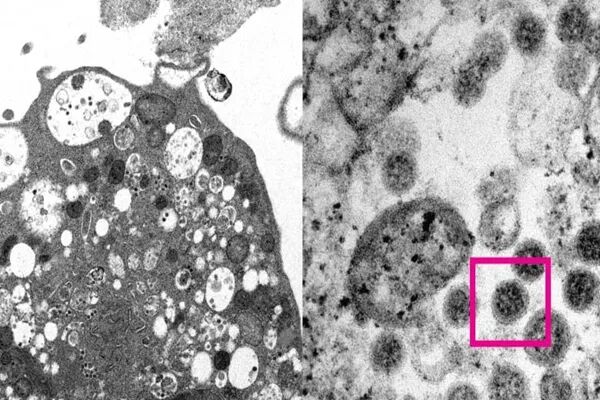

自世卫组织报告发现“奥密克戎(Omicron)变种亚系BA.2”后,全球已有47个国家/地区报告病例10,000多宗。奥密克戎(Omicron)变种亚系BA.2”又被称为“奥密克戎妹妹”,该变种于去年11月被首次发现,上周五被英国卫生安全局 (UKHSA) 指定为“正在调查的变种病毒”。加拿大公共卫生局(PHAC)周二证实,截至目前,加拿大已发现51例BA.2变体病例,感染者主要来自国际旅客。

奥密克戎(Omicron)变种B.1.1.529有四个子系:BA.1、BA.1.1、BA.2和BA.3。世卫组织称,迄今为止,BA.1占全球奥密克戎病例的绝大多数。加拿大公共卫生局(PHAC)发言人Anne Genier表示,BA.2与BA.1有许多相似之处,但也确实存在差异——这些突变差异或将导致其在“传播快慢、检测难易以及可能发生的免疫逃逸”等方面出现不同结果。

BA.2病例最早在丹麦、挪威及英国等地迅速飙升。据相关国家早期研究报告显示:· 与奥密克戎变种BA.1相比,BA.2增长强劲。目前,除了发现“BA.2比BA.1更具传染性”外,该病毒的其它特性尚不清楚。(挪威研究)· BA.2被一些科学家称为“隐形奥密克戎”,因为BA.2更难在PCR检测中被检测出来。(挪威研究)· BA.2似乎并不比BA.1更能引起更严重的疾病。(挪威研究)· 与BA.1相比,BA.2的住院率没有差异。(丹麦研究)· 英国卫生安全局 (UKHSA)COVID-19事件主管Meera Chand博士则强调,目前数据有限,下结论为时过早。目前,BA.1浪潮已在包括加拿大在内的世界大部分地区出现登顶迹象。科学家们正在密切关注奥密克戎变种其它子系的传播情况。UBC传染病专家Horacio Bach博士表示,奥密克戎变体相关子变体出现,不足为奇,因为新冠病毒一直在全球范围内疯狂繁殖,新的变种迟早出现。蒙特利尔大学病毒学家Levon Abrahamyan表示,所有病毒都会发生变异,而且所有变种都会伴之以“基因组成不同但具有共同起源的亚变种/子系”。